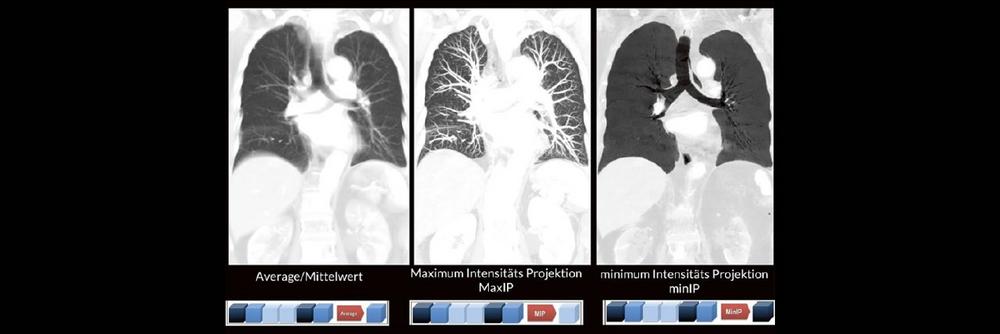

Darüber hinaus werden die unterschiedlichen MPR-Techniken wie z. B. Maximum Intensitäts- Projektionen (MaxIP´s) und minimum Intensitäts Projektionen (minIP´s) oft nicht routinemäßig angewendet. Dabei können verschiedene Pathologien durch den zielgerichteten Einsatz der unterschiedlichen MPR-Techniken oft viel einfacher und besser diagnostiziert werden.

- Maximum Intensität Projektion

- Minimum Intensität Projektion